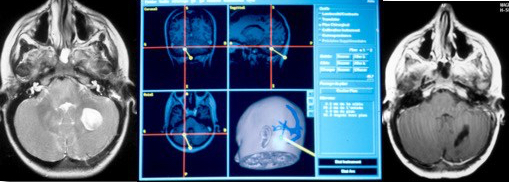

dans quelques cas (tumeurs de découverte fortuite, dans la NF1, récidive de faible volume), la neuronavigation peut être utile car la tumeur est petite.

l’examen histo-pathologique extemporané est souvent utile, car si la tumeur infiltre des régions délicates (pédoncule cérébelleux, V4), il est préférable que l’exérèse reste incomplète.